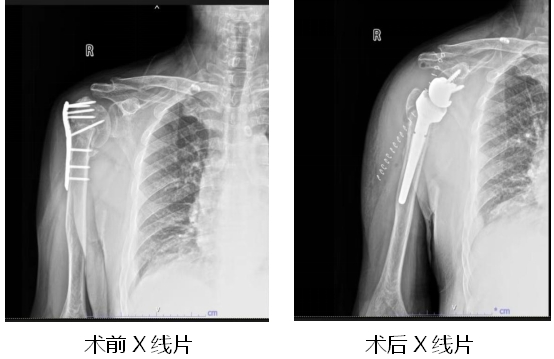

近日,一位60多岁的大爷因右肩关节疼痛,活动受限明显向湖北省第三人民医院(湖北省中山医院)骨外科主任王显勋求助。原来,大约一年前,大爷因外伤致右侧肱骨骨折在外院做过手术,但在恢复期间出现了关节疼痛,活动时疼痛不适。入院经检查判断大爷为“右肱骨头缺血性坏死、右肱骨骨折不连接、右肩关节粘连”。由于患者已在院外进行右侧肱骨骨折钢板内固定术,手术有一定难度,王显勋组织科内进行病例讨论,为患者制定手术方案。在做好充分的术前准备后,王显勋带领副主任黄飞、副主任医师万昌涛等骨科团队为患者行“右侧肱骨内固定装置去除术+反向全肩关节置换术”。术后,护理团队精心指导患者功能锻炼,预防其他并发症发生,患者恢复良好,对治疗效果和护理服务非常满意。